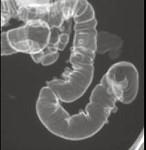

男,52岁,习惯性便秘2年余,结合图像,应诊断为 ( )A.溃疡性结肠炎B.结肠憩室病C.假膜性结肠炎D.结肠息肉病E.结肠转移瘤

问题 男,52岁,习惯性便秘2年余,结合图像,应诊断为 ( )

选项 A.溃疡性结肠炎 B.结肠憩室病 C.假膜性结肠炎 D.结肠息肉病 E.结肠转移瘤

答案 B